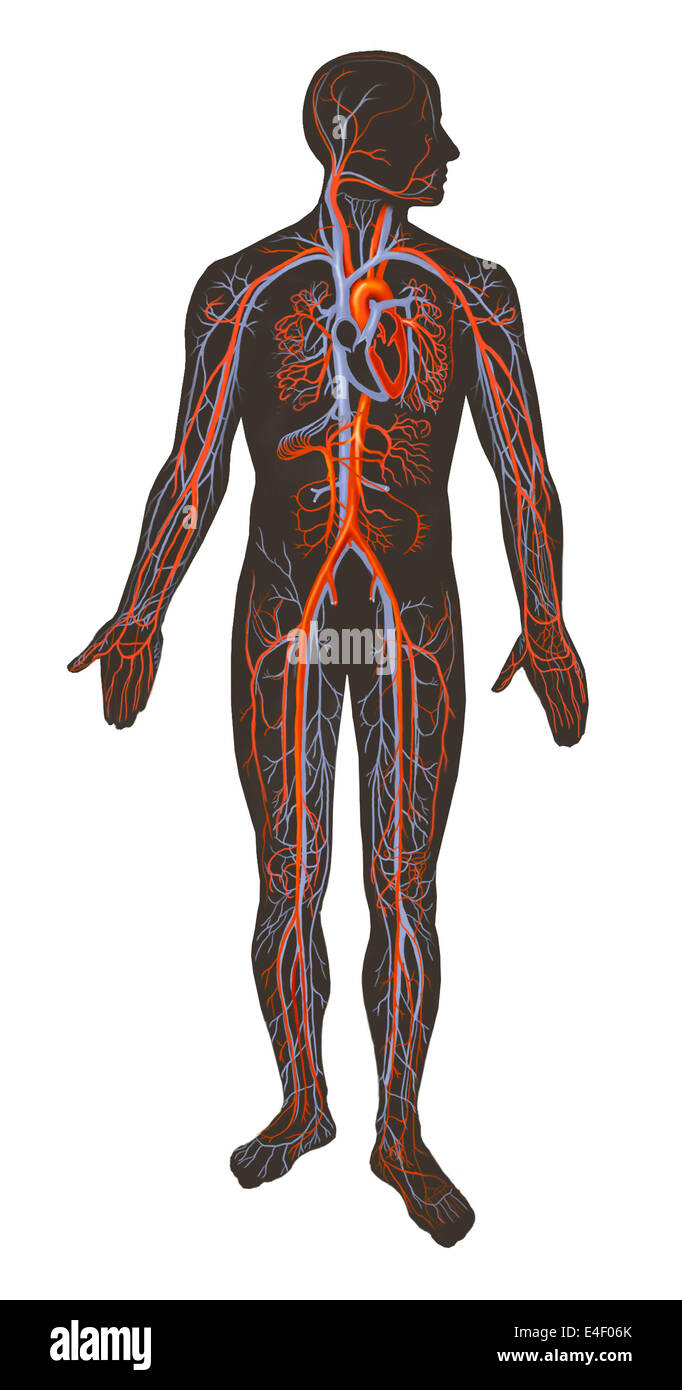

Arteries and veins of the human body. Stock Photohttps://www.alamy.com/image-license-details/?v=1https://www.alamy.com/stock-photo-arteries-and-veins-of-the-human-body-71629563.html

Arteries and veins of the human body. Stock Photohttps://www.alamy.com/image-license-details/?v=1https://www.alamy.com/stock-photo-arteries-and-veins-of-the-human-body-71629563.htmlRME4F06K–Arteries and veins of the human body.